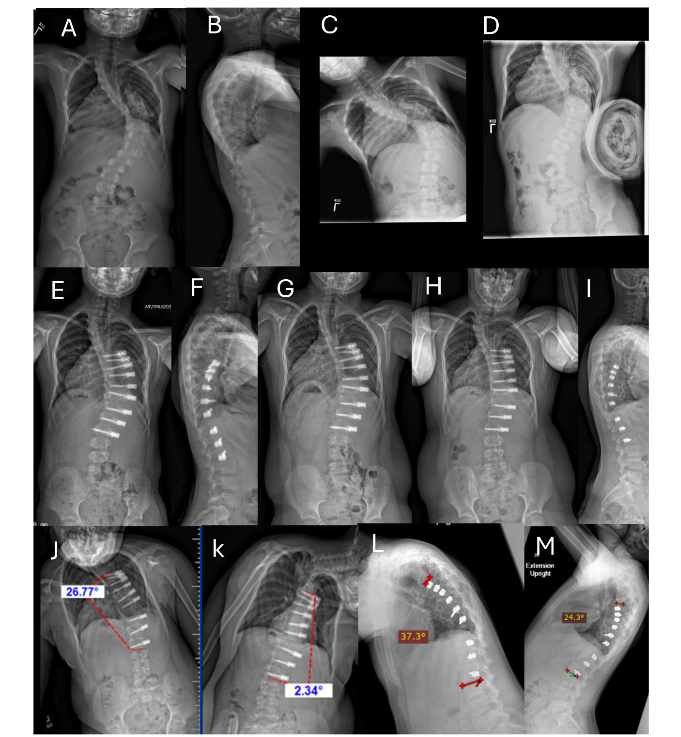

Since 2014, ASC with anterior longitudinal ligament and annular disc complex (intervertebral) de-tethering releases has been employed through a modified anterior thoracic approach which provides both compression across the convexity and effective derotation. This technique of screws and pliable cords is designed to circumvent the limitations associated with VBT, such as limited curve correction, operative curve size requirements, and the reliability to achieve significant restoration or correction of the deformity.

Intervertebral de-tethering releases (IDTR) are performed under general anesthesia with the patient in a prone position. The anterior longitudinal ligament and annular disc complex are approached through a lateral thoracotomy. For patients with double curves, the intervertebral de-tethering releases are performed where necessary to improve curve correction and increase curve derotation for correction of thoracic hypokyphosis.

The intervertebral de-tethering releases are intended to preserve the disc complex; we do not remove the cartilaginous end plate nor do we extend from the T10-L2 region.